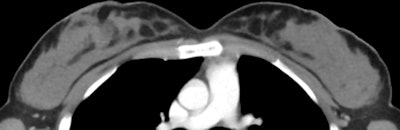

Axial CT images of a 70-year-old woman with grade 1 CT breast density (above) and a 42-year-old woman with grade 4 (below). All images courtesy of Radiology.